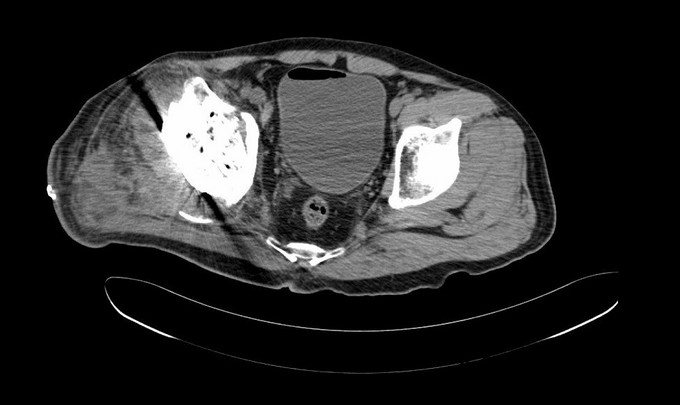

查体:右髋关节前方可见约13X2CM、后外侧可见约23X1CM手术切口瘢痕。右下肢短缩。双侧髋关节周围皮温正常,温、痛觉灵敏。局部软组织柔软。双侧髋关节周围无压痛,被动屈伸、内外旋及内收外展可,无内外旋诱发痛。双下肢足背动脉搏动正常。右髋后方较左侧松弛,可触及股骨头。右下肢短缩5cm。右髋关节屈120度,伸0度,内外旋40°,外展30度,内收20度。左髋关节屈130度,伸0度,内外旋40°,外展30度,内收20度。右下肢外展肌力3级。双下肢无轴向叩击痛。双侧直腿抬高试验(-),双膝、双踝关节活动正常。 辅助检查:X线;05年10月 示右股骨头变形,右髋关节间隙变窄。05年11月 右股骨头塌陷,关节间隙变窄,右髋关节腔周围可见游离骨块。05年11月,右股骨头消失,右髋关节腔内游离骨块 05年12月,右股骨头缺如,右股骨颈上段部分缺失,右髋关节腔内游离骨块减少。06年3月,右股骨颈进一步缺失,大转子上移,臼缘骨质增生。06年7月,右全髋置换术后,06年11月示右髋置换术后假体位置尚可,07年8月示髋臼假体移位,股骨柄下沉,股骨上段皮质增生,可见骨膜反应。07年11及12月,可见髋臼及股骨柄周围骨溶解,假体松动,人工关节脱位。08年1月及4月 右髋临时骨水泥假体固定术后松动移位,髋臼及股骨侧骨溶解。08年9月示右髋二期翻修术后,假体位置良好。08年12月 部分右髋臼螺钉松动,臼杯松动,09年2月示部分右髋臼螺钉断裂,臼杯松动,03年3月大量右髋臼螺钉断裂,臼杯明显移位,外移、右髋脱位。09年9月及12月见臼杯破裂。

诊断:1、右髋结核病灶清除术后右全髋置换术后感染翻修术后假体松动、髋关节脱位、髋臼骨缺损。(AAOS III型)右下肢短缩。2、右髋Charcot 关节病? 治疗:右髋关节置换术后右股骨头假体取出、右髋臼骨缺损结构骨移植、颗粒骨打压植骨,cage、加强环骨水泥髋臼重建,股骨端假体颈延长、股骨头置换术。